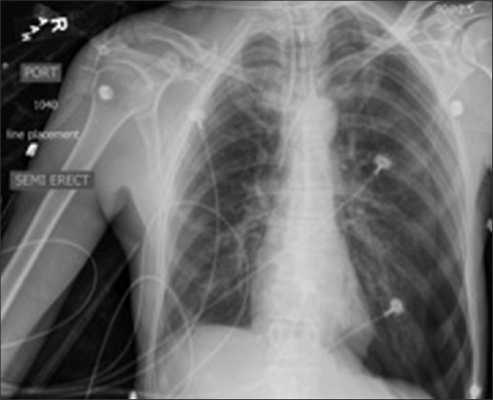

Ипсилатеральный пневмоторакс

Контралатеральный пневмоторакс